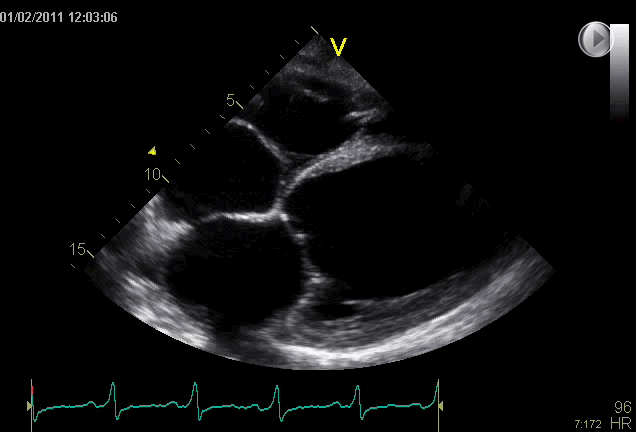

SC

EEU case image missing

Subcostal View with Severely Reduced Left Ventricular Function: This clip demonstrates that left ventricular function can also be evaluated from the subcostal (SC) view. The very dilated left ventricle, almost no contraction, severely reduced movement of the mitral valve leaflets, and lack of longitudinal function make it clear that the heart is suffering heavily. Both the left and right atria are also dilated, indicating severe heart failure. With training, eyeballing here makes it obvious at first glance that the heart is in significant distress.